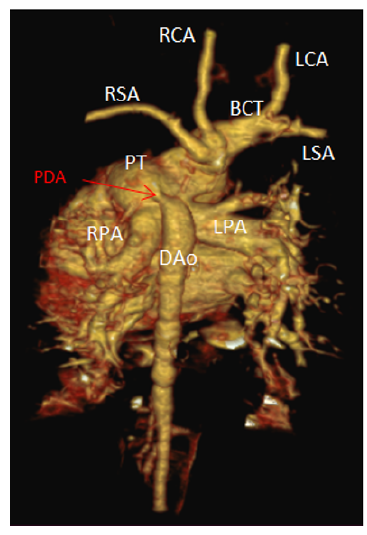

The Berry Syndrome: A Cardiovascular Malformation: A Case Report

Halfi Mohamed Ismail, Lrhorfi Najlae, Aseri Naila, Cheikhaoui Younes and Chat Latifa. 10(4): 48-52.